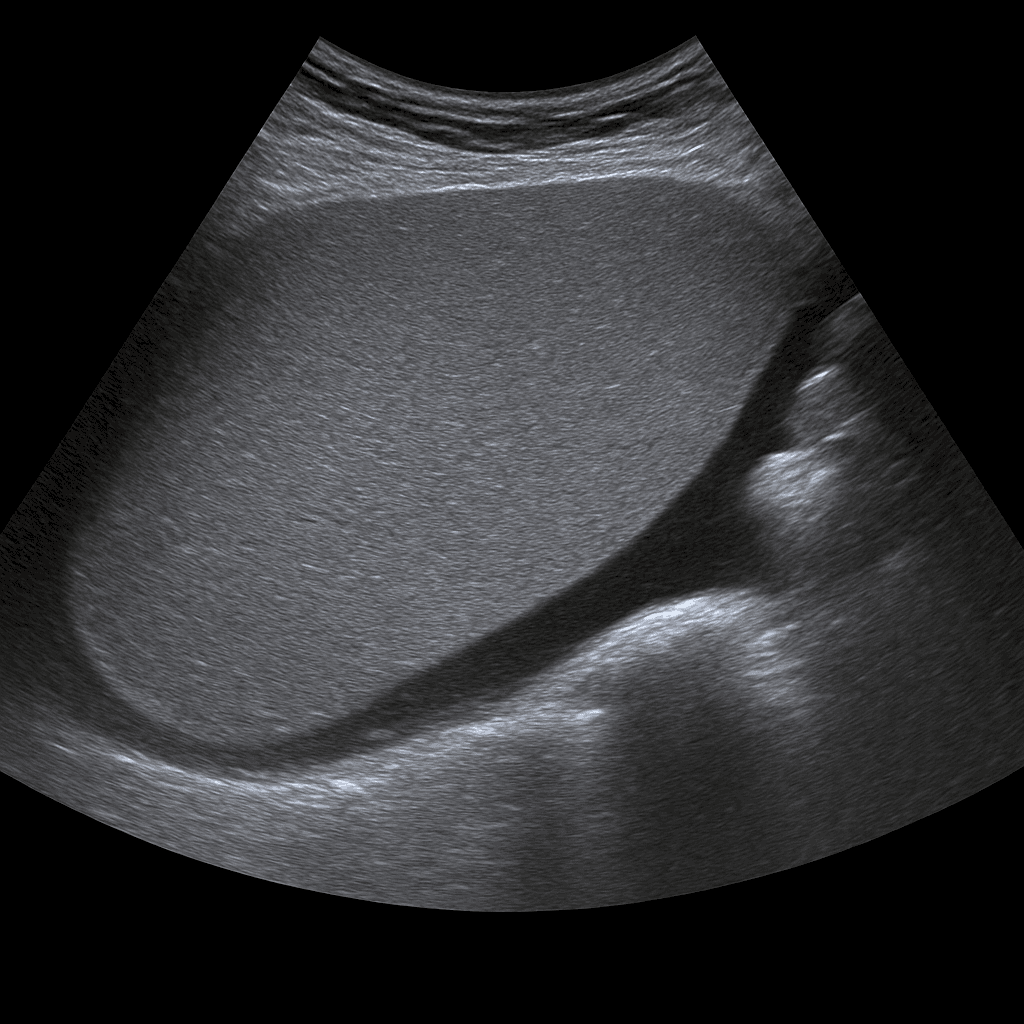

Ett ultraljud av mjälten används för att undersöka mjältens storlek, form, vävnadsstruktur och blodflöde. Undersökningen utförs av specialistläkare inom radiologi och ger detaljerade bilder i realtid som kan visa tecken på förstoring, cystor, infarkter eller andra förändringar. Ultraljud mjälte används ofta för att utreda orsaken till buksmärta, infektion, anemi, misstänkt förstorad mjälte (splenomegali) eller som del av en utredning av lever- och blodsjukdomar.

Undersökningen utförs medan du ligger på rygg eller på höger sida. En gel appliceras på huden och läkaren för ultraljudsproben över området under vänster revbensbåge. Mjälten avbildas i olika vinklar för att bedöma storlek, vävnad och kärlflöde. Vid behov kan även lever och njure på vänster sida granskas som jämförelse.